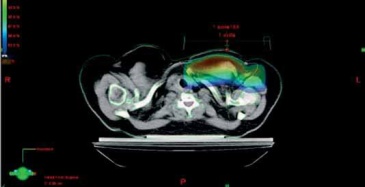

- Využívat modifikátorů svazku záření: klínových filtrů anebo

kompenzátoru (Wilks R. J. 2002) k získání větší dávkové homogenity

v oblasti prsu, stínících bloků standardních anebo individuálních,

MLC k tvarování svazku záření (obr. 2). Výhodné je využívat vážení

polí.

- Podle rozměrů pacientky volit vyšší energii X záření pro

tangenciální pole (u velké vzdálenosti mezi CP tangenciálních poli

22 cm a více) nebo i u axillárního pole (příliš hluboké PTV): např.

6X + 18X nebo 6X + 6X technika pole v poli nebo 18 X (zvážit

použití bolusu). (obr. 3a, b, c, obr. 4a, b).

Obr. 4a Optimalizace RT tangenciální pole X záření en. 6 MV s MLC a bez MLC

Obr. 4b Optimalizace RT X záření en.18MV+ 6MV tg pole s MLC a bez MLC